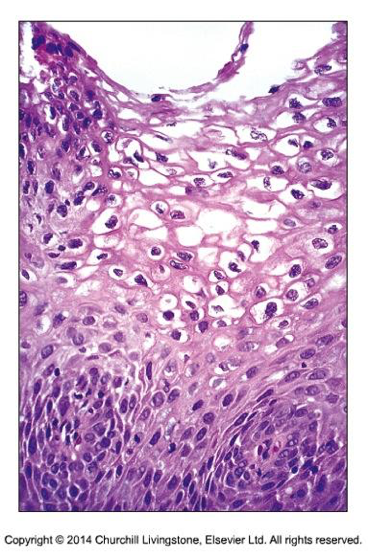

Histopatologi: Histomorfologiskt ser man en proliferation av basala och parabasala celler som kan vara minimal, men som även kan sträcka sig upp till en tredjedel av epitelets tjocklek (Fig PAT-1). Mitoser ses mest inom de mer parabasala delarna av epitelet och atypiska mitoser saknas. I de ytliga delarna av epitelet ses ökad mängd cytoplasma, dock är kärnstorleken bevarad så att kärn-cytoplasma-ration minskar.

Figur PAT-1: Histologi av LSIL [6]Bilaga 7. 4.1 Figur1.png

Bilaga 7. 4.1 Figur2.png